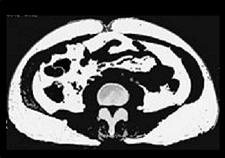

オプション CT撮影による内臓脂肪測定 3850円

皮下脂肪型 内臓脂肪型

※白い部分が脂肪